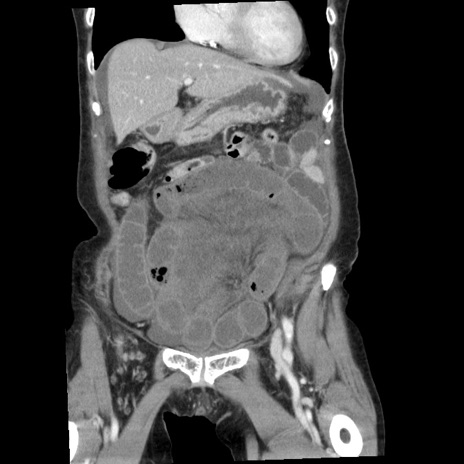

症例1(冠状断像)

【症例】80歳代女性

【主訴】腹痛

【現病歴】8時間前から腹痛あり来院。

【既往歴】糖尿病、脂質異常症、子宮体癌にて子宮全摘術

【身体所見】意識清明・会話良好だが腹痛で苦悶様、全腹部にわたって反跳痛と圧痛あり

【データ】WBC 13600、CRP 0.14、LDH 224、CK 90